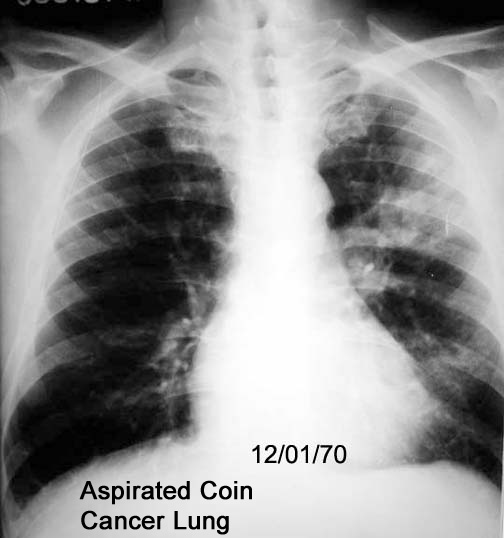

Labeled Image I treated this patient as having lung abscess secondary to aspirated coin. The cavity turned out to be due lung cancer.

Moral: Close follow up until the problem is resolved.